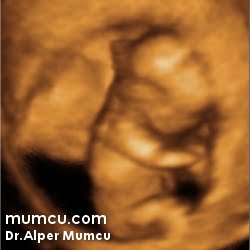

3 Boyutlu ultrason resimleri

Bu sayfadaki fotoğraflar degişik zamanlarda ve farklı hastalarda Dr. Alper Mumcu tarafından çekilmiştir.

10 haftalık gebelik